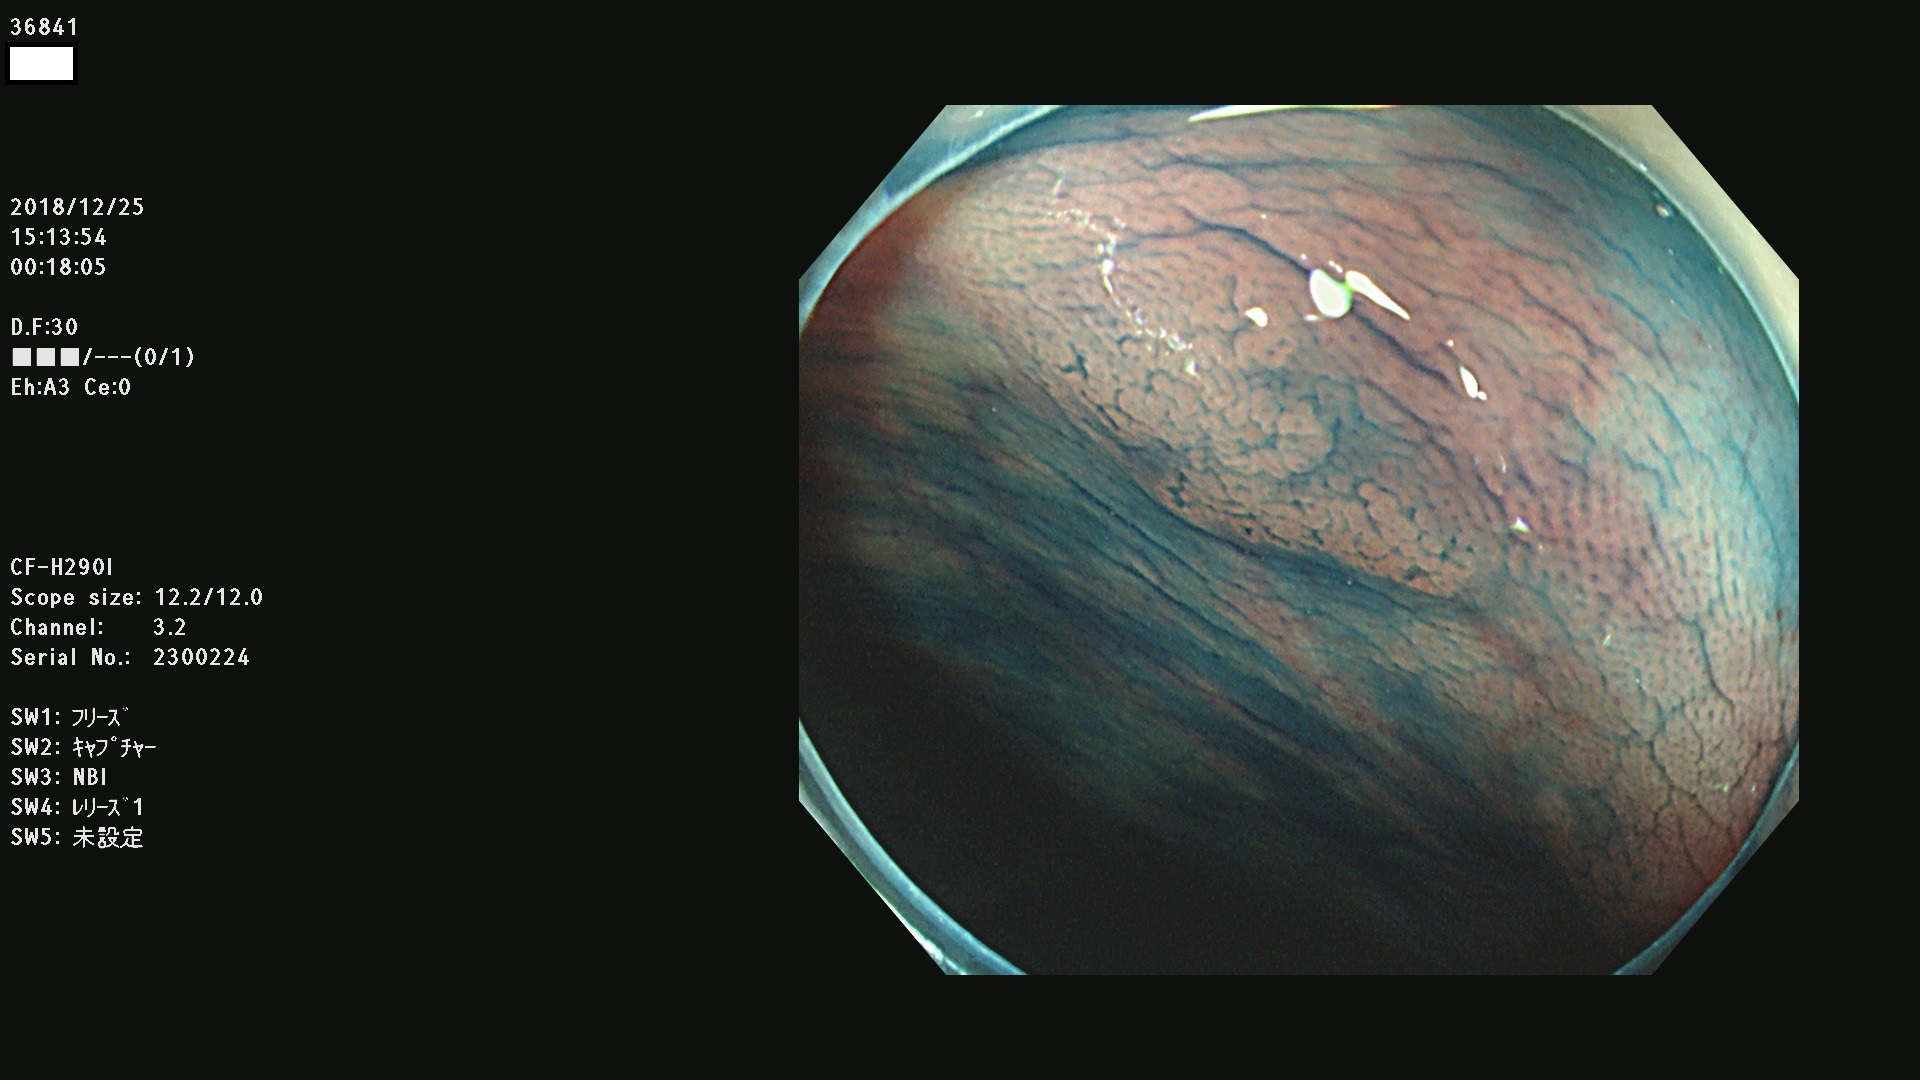

発見困難で危険性の高い平坦型病変(上記100名より抽出)

36804 36806 36807 36808 36809 36810 36811 36813 36815 36816 36817 36818 36820 36821 36822 36824 36825 36826 36828 36829 36830 36831 36832 36833 36834 36835 36837 36840 36841 36842 36845 36846 36848 36849 36851 36852 36853 36854 36855 36857 36859 36860 36861 36862(SSAPのみ) 36863 36864 36866 36868 36869 36870 36873 36875 36877 36878 36879 36881 36882 36883 36884 36885 36886 36887 36888 36889 36891 36892 36893 36894 36895 36896 36897 36898 36899